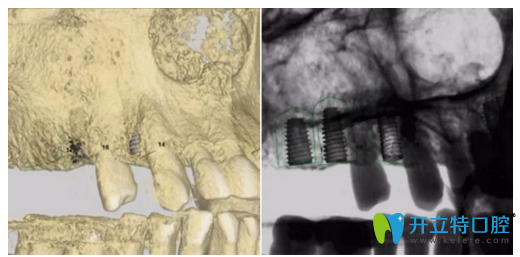

▲ 患者口內(nèi)3D圖拍攝

▲ 患者左上6牙位模擬種植圖

▲ 患者左上4牙位模擬種植圖